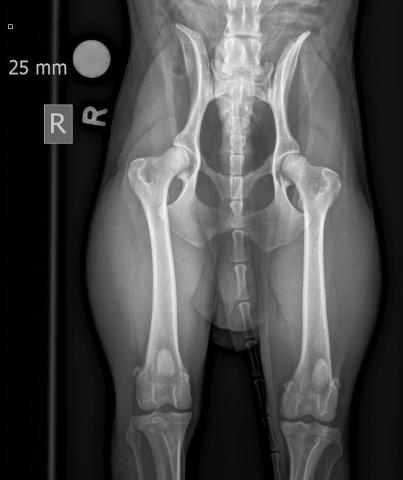

• ED Abklärungen

HD und ED Beurteilungen werden nach Wunsch des Besitzers oder nach Vorgaben der Rasseklubs jeweils von der HD-Kommission in Zürich oder Bern beurteilt. Für unsere deutschen Kunden ist auch ein Versand nach Deutschland möglich